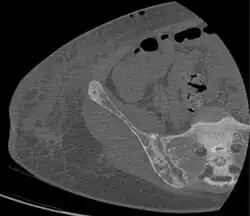

CT shows focal areas of osteosclerosis.[18] -